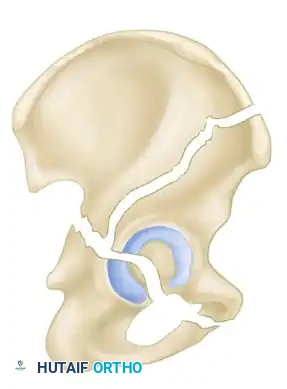

- Both-Column Fractures: The most complex pattern. All articular segments are detached from the intact posterior ilium (which remains attached to the sacrum).

Clinical Pearl: The Spur Sign

In a both-column fracture, the intact portion of the ilium (attached to the sacroiliac joint) projects laterally relative to the medially displaced, fractured acetabular columns. On an obturator oblique radiograph, this intact bone appears as a sharp spike, known as the "Spur Sign." Its presence is pathognomonic for a both-column fracture.

Secondary Congruence in Both-Column Fractures

A unique phenomenon observed exclusively in both-column fractures is "secondary congruence." Because all articular fragments are detached from the axial skeleton, they can occasionally settle concentrically around the medially displaced femoral head.

If the articular cartilage space is preserved and the femoral head remains concentrically enveloped by the fragments (despite medialization of the entire joint complex), nonoperative treatment via skeletal traction can yield surprisingly excellent long-term functional results.